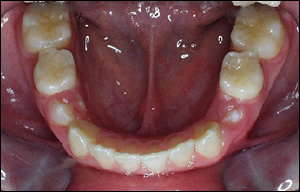

Fig 1: A 9 year old female presented with a lack of adequate space in her lower dental arch. This resulted in crowding of the lower incisors.